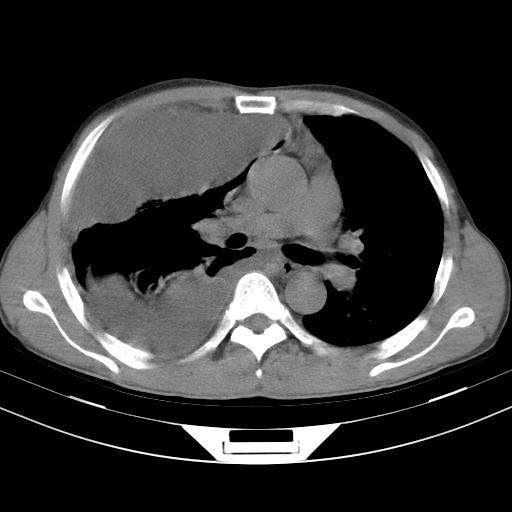

男性,44岁,结核病史多年。现胸闷气短,咳嗽,偶咳血。

1)两肺继发性肺结核伴空洞形成,左肺多发性结核球。2)右侧大量胸腔积液伴右肺部分膨胀不全。3)纵隔淋巴结肿大。

支持1)两肺继发性肺结核伴空洞形成。2)右侧大量胸腔积液伴右肺部分膨胀不全。3)纵隔淋巴结肿大

吉大一院胸水抽检结果:结核性胸水